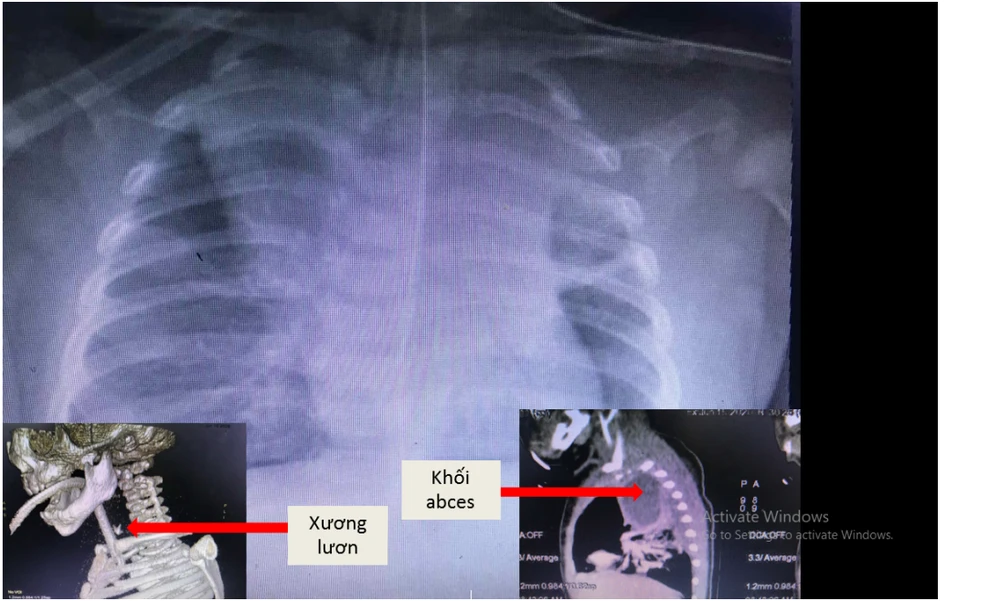

Kết quả chẩn đoán hình ảnh ghi nhận bé bị áp xe thành sau họng lan xuống 1/3 trung thất sau, viêm phổi, ghi nhận có dị vật ở thực quản và đường dò từ thực quản ra khối áp xe. Bé được hội chẩn các ê kíp hô hấp, tiêu hóa, tai mũi họng, ngoại lồng ngực để tiến hành rạch cạnh cổ thoát lưu mủ khối áp xe.

Hình ảnh khối áp xe và vị trí dị vật trong thực quản bé trai bị hóc xương lươn. Ảnh: BVCC

Khi nội soi, các bác sĩ gắp ra được dị vật là một mảnh xương lươn (0,5x0,3cm) gắm sâu vào thành thực quản và gây rách một đoạn khoảng 2cm, phải khâu vá lại. Sau hơn một tháng điều trị, tình trạng trẻ cải thiện dần, cai được máy thở, tỉnh táo, vết thương cạnh cổ, thực quản hết mủ dịch, lành lặn và chuẩn bị được cho ăn qua đường miệng trở lại.